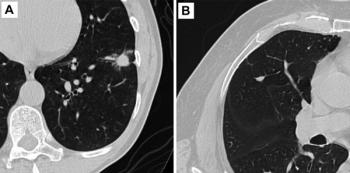

A new study revealed that an emerging artificial intelligence (AI)-enabled software tool led to improved sensitivity, specificity and inter-observer agreement for the diagnosis of indeterminate pulmonary nodules on chest computed tomography (CT) scans.